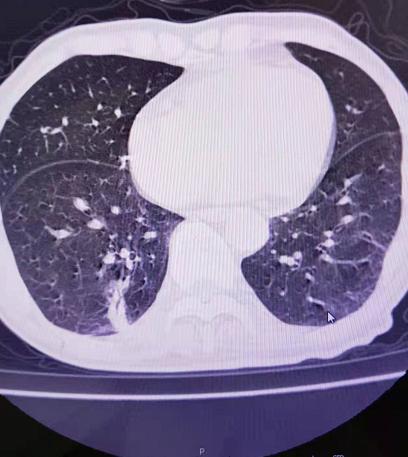

韩某,男,86岁,1年前体检发现右肺下叶肺结节,复查进展,既往糖尿病、高血压30余年,口服药物控制可。

因患者高龄,基础病多,不适合手术治疗,经充分沟通,拟行氩氦刀冷冻消融术。

术中经皮局麻下插入氩氦刀冷冻消融针2根,2个循环冷冻后CT可见冷冻范围完全覆盖肺内肿物。术后患者无明显疼痛,观察2天后出院。